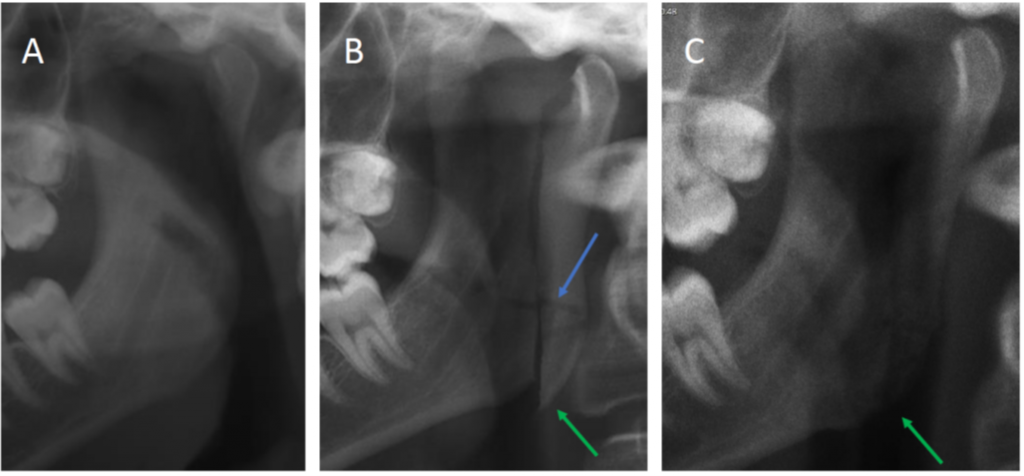

図 1: 修正顆状突起切開術を示す OPG。 A) 手術前の患者。 B) 術後結果、手術から 2 週間後に撮影した OPG。切歯から角まで骨切りが行われました。この場合、2つの骨片は、Hall法[6]に従って、放射線学的にコントラストのない粗い縫合糸(青い矢印)で固定されています。 C) 術後 1 年経過し、正常な治癒が見られます。近位セグメントの最下部が吸収されていることに注意してください。緑の矢印はエリアを示しています。